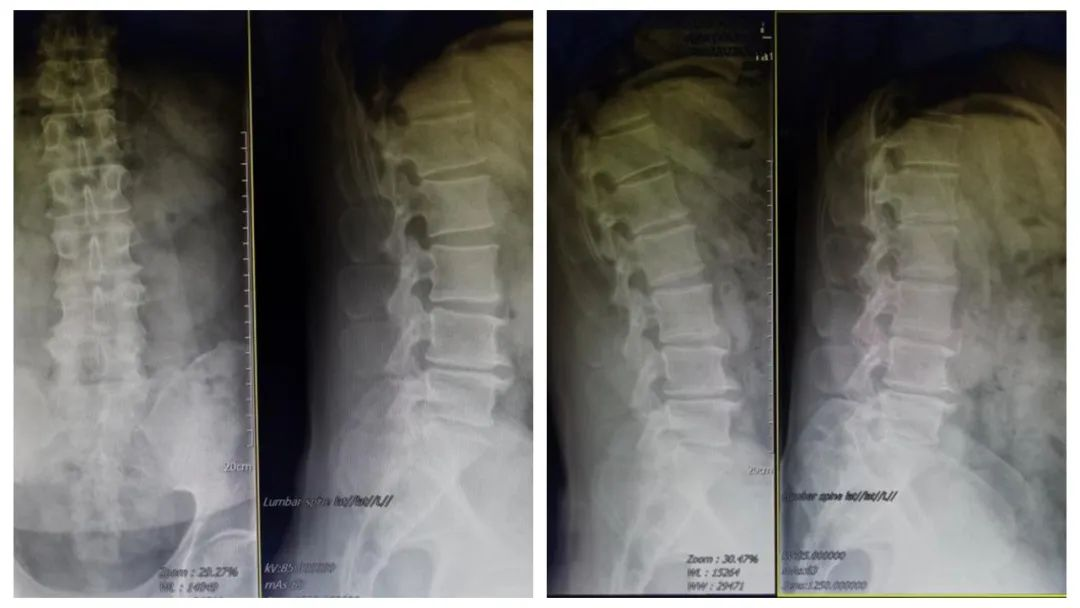

术前影像学检查:腰5/骶1椎间盘突出症术后改变,腰5/骶1椎间盘突出术后再复发